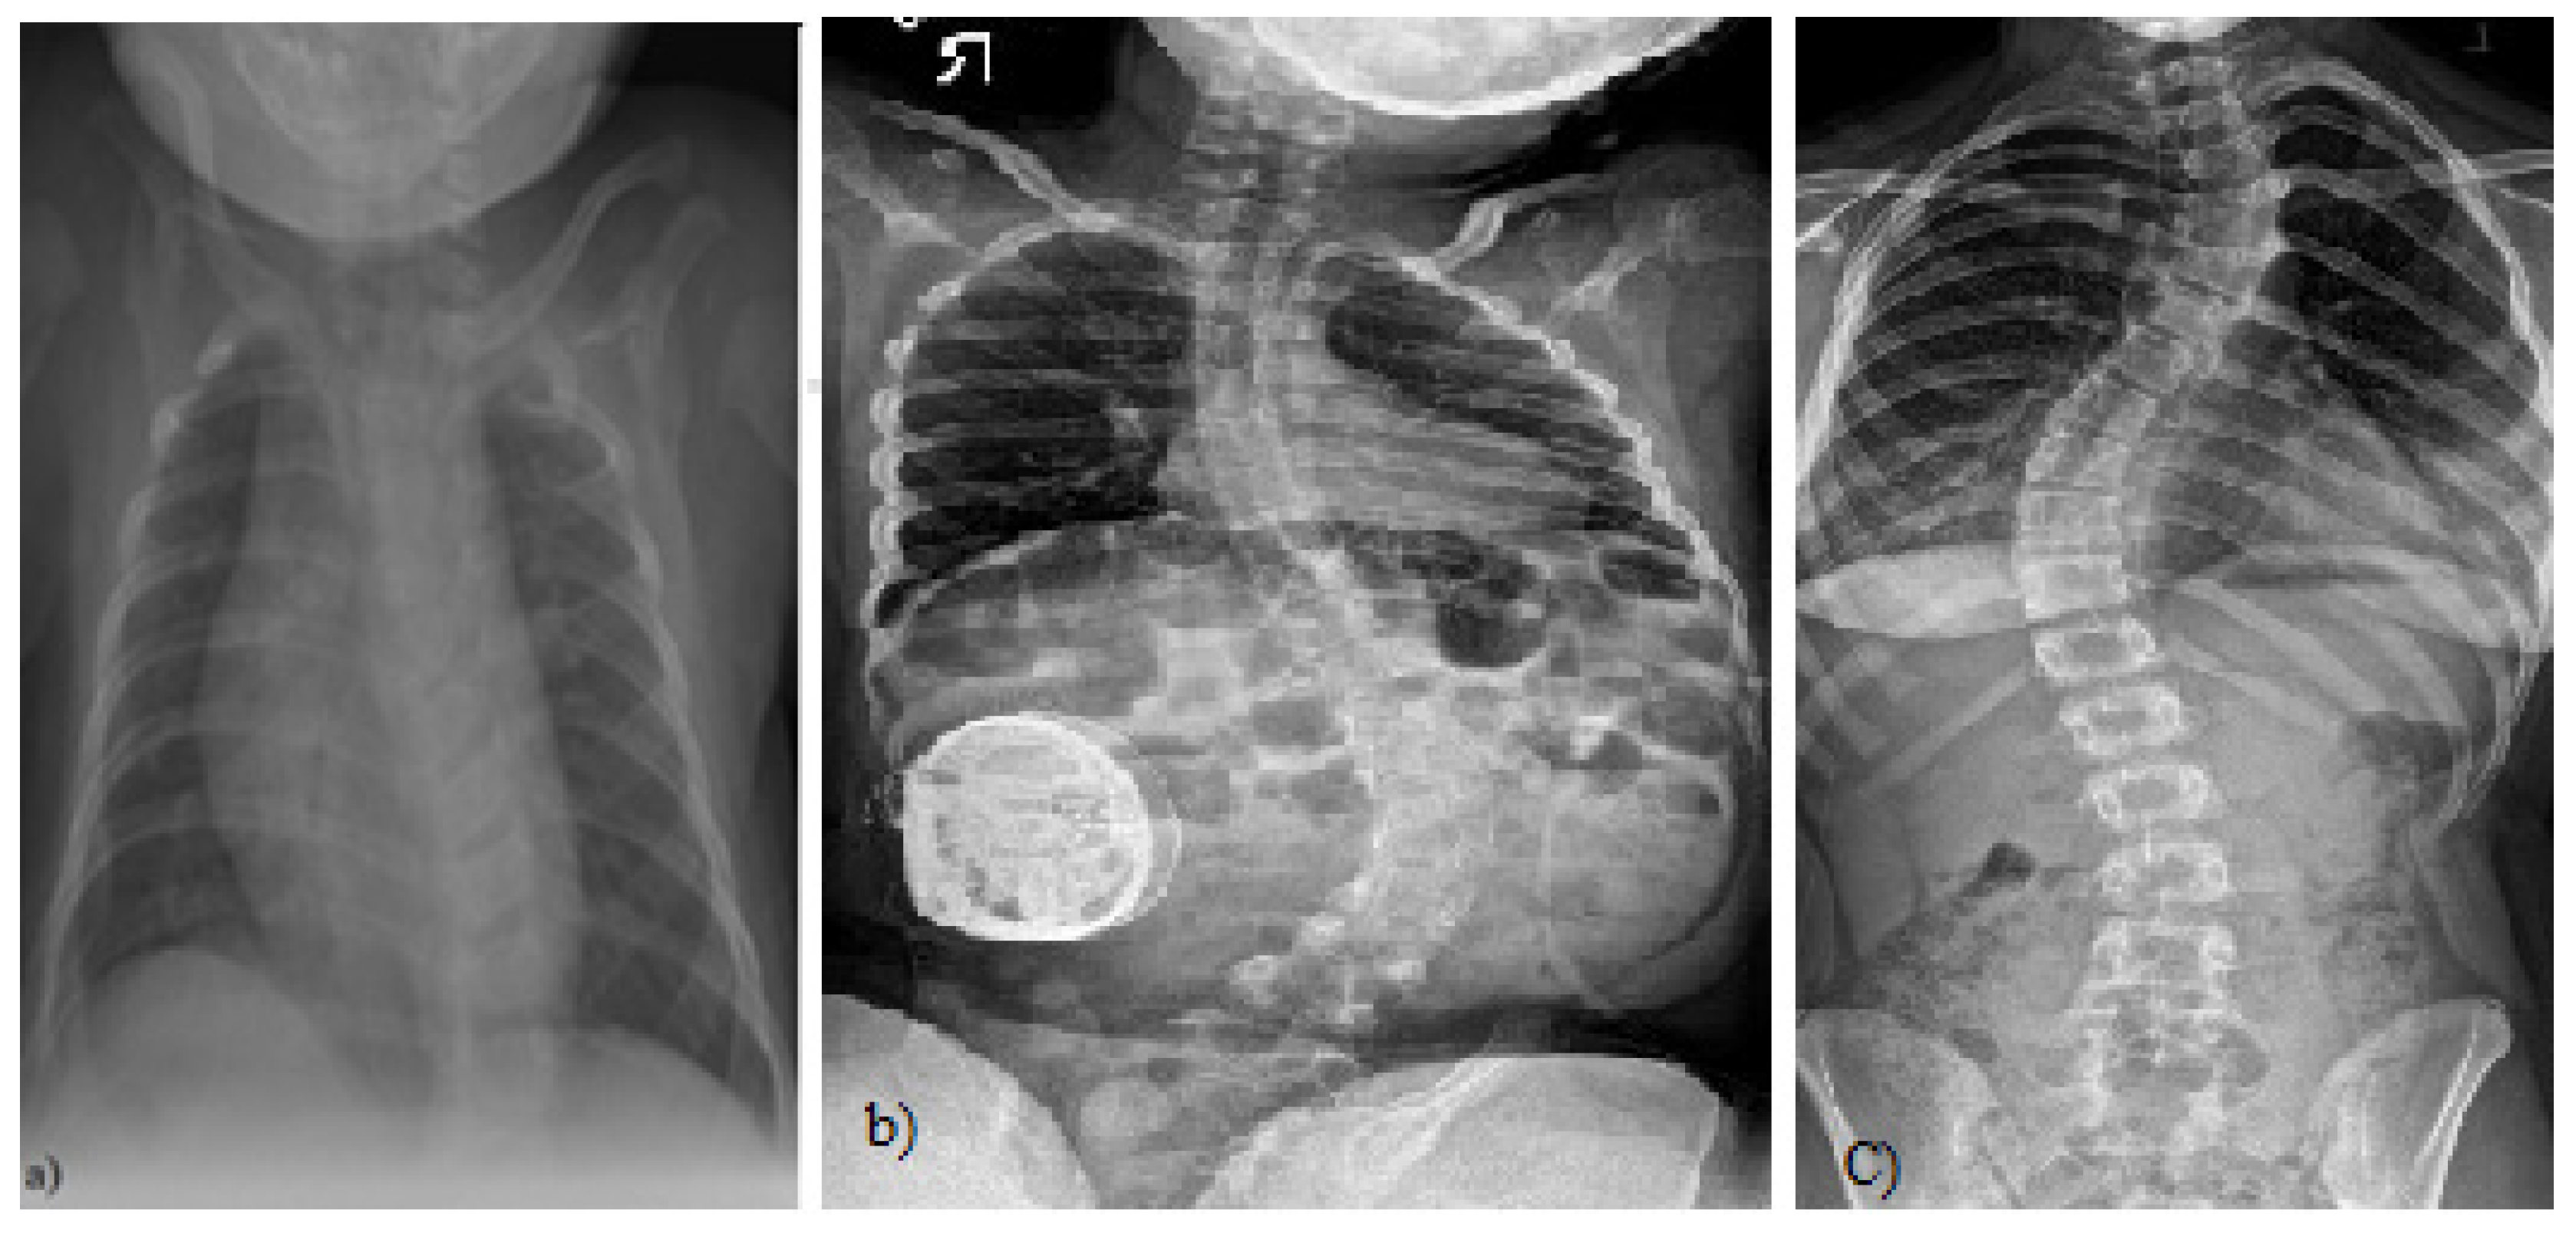

Figure 1.

(a) A 4-month-old boy born small for gestational age, at 37 weeks, who presented initially with asymmetry of both the left and right aspects of the anterior and posterior chest and confirmed thoracolumbar scoliosis and vertebral anomalies based on plain radiography with a Cobb angle measurement of 30 degrees, (Case courtesy of Sonal Desai, Radiopedia.org, rID: 63310 under Creative Commons License (CC BY 3.0).) [5]; (b) X-rays of a girl with juvenile idiopathic scoliosis, (Case courtesy of Dr Jeremy Jones, Radiopaedia.org, rID: 89566 (CC BY 3.0).) [6]; and (c) severe left thoracic adolescent scoliosis, (Case courtesy of Dr Jeremy Jones, Radiopaedia.org, rID: 89456 (CC BY 3.0).) [7].